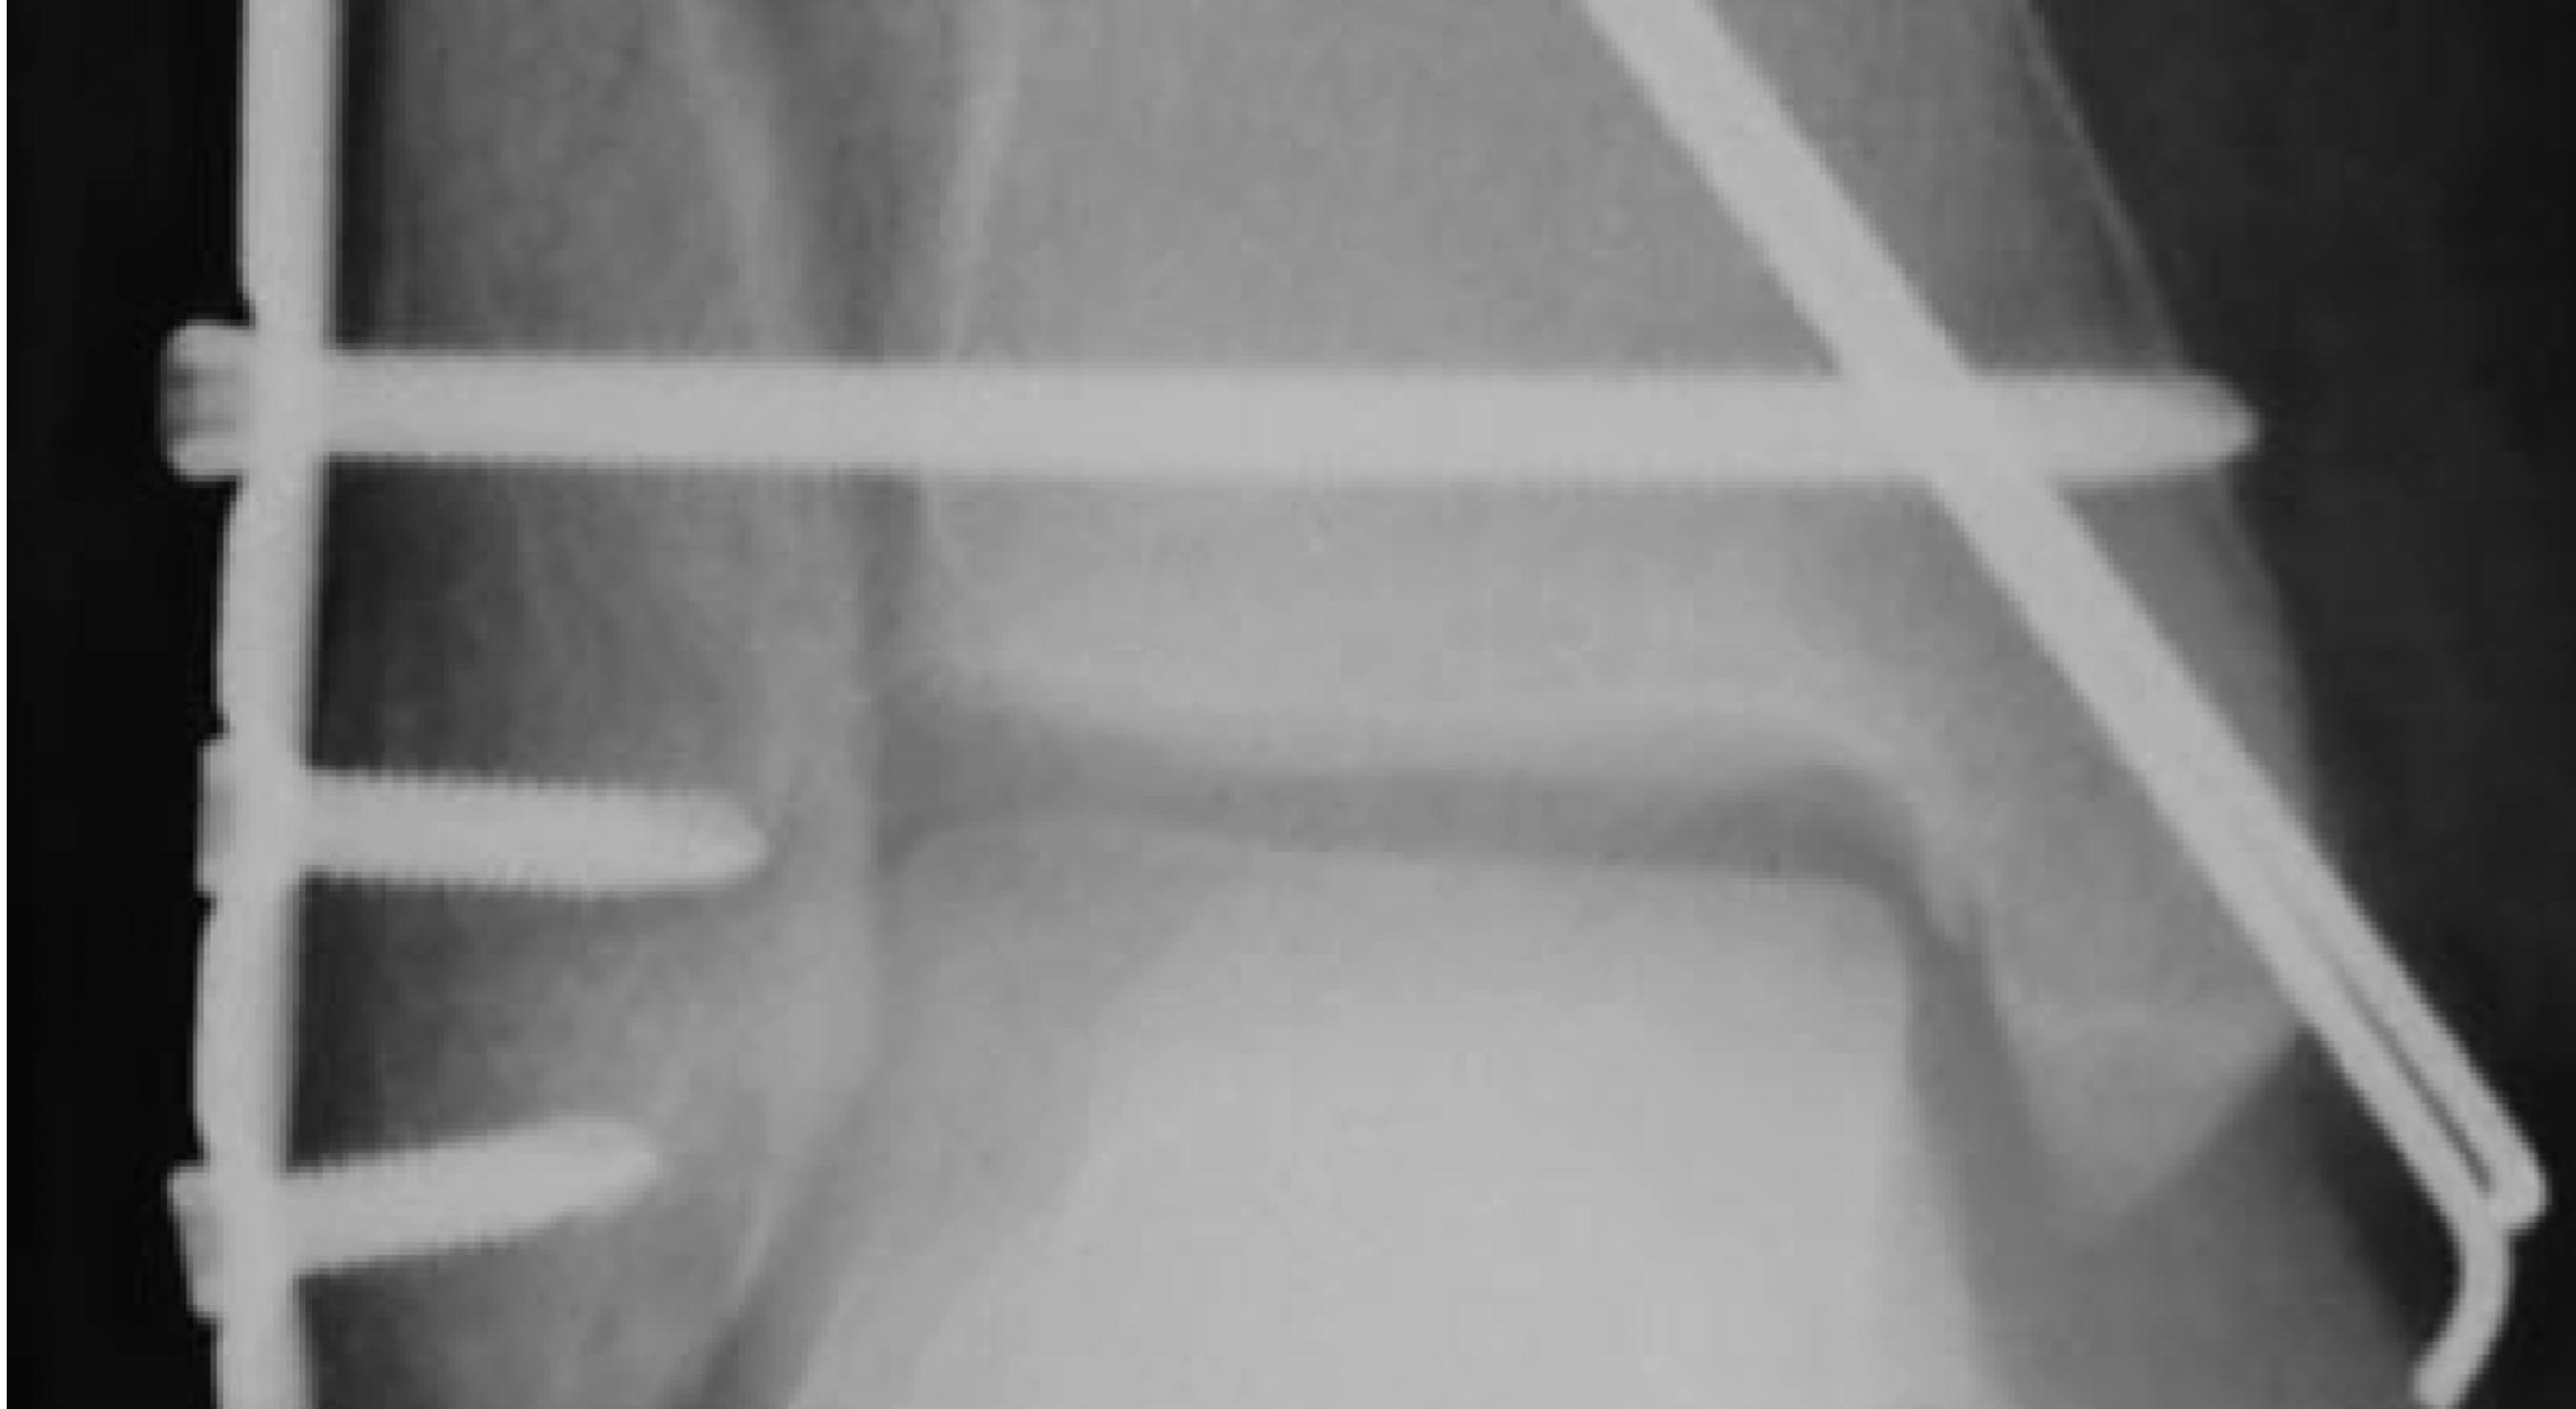

Межберцовый винт: в его качестве locking had screw, а не обычный кортикальный? В каких руководствах или статьях есть такая рекомендация?

Вопрос не очень понятно сформулирован. Что не так? Поставлен обычный кортикальный не блокированный в пластине винт. Во вложении - фото отрывка из руководства по внутреннему остеосинтезу АО. В переводе А.В. Королева.

Как раз там рекомендуется введение обычного 3.5 мм шурупа через оба кортикальных слоя большеберцовой кости.

Этот винт проведен через сам синдесмоз на 1 см проксимальнее сустава - а это в соответствии с какими рекомендациями?

Во вложении рентгенограмма из руководства Кэмпбэлла, издания 2013 г. (стр. 2623), демонстрирующая технику фиксации синдесмоза через отверстие в пластине. Расстояние от суставной линии там явно не 2 см. тем более не 3.

Ну, хорошо, Кэмпбелл так Кэмпбелл.- Согласно этому руководству 13-го издания хоть и не 3-4, но все же на 2-3 проксимальнее tibial plafond (не суставной щели!) (см. приложение)